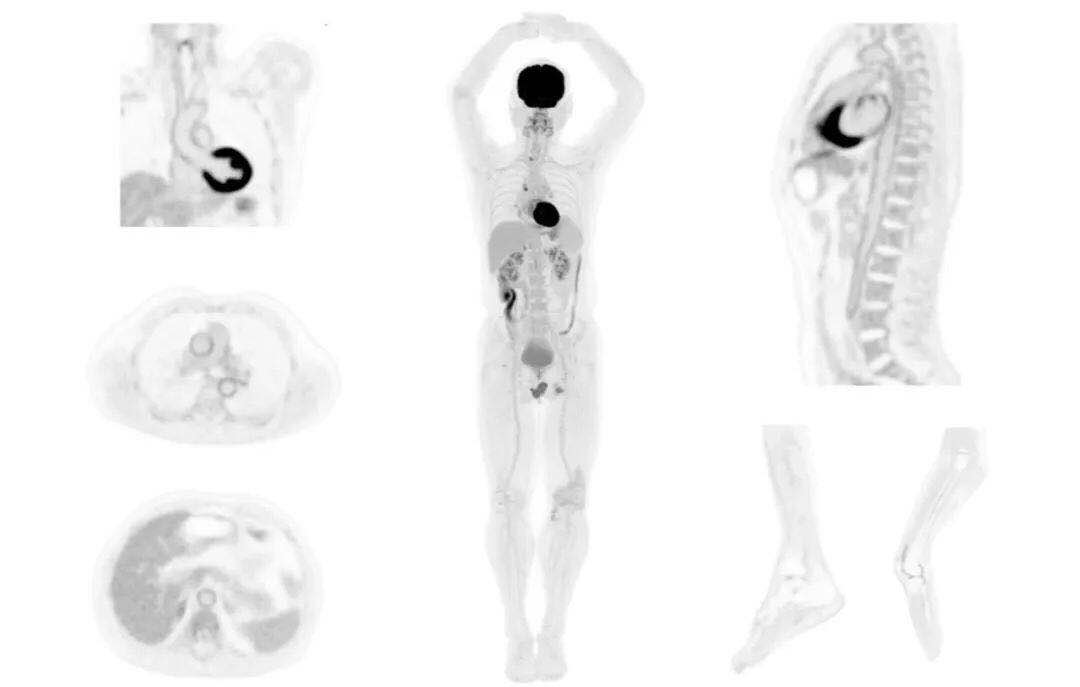

uExplorer探索者不再局限于傳統(tǒng)靜態(tài)代謝過程3D成像,而是在此基礎上新增一個維度——時間,從而實現(xiàn)4D全景成像。

注射總劑量為7.8mCi,14分鐘全身采集時間,在擁有超高靈敏度與超高分辨率的uEXPLORER上,即可得到展示顯示人體諸多精細結構的高清三維圖像。

注射總劑量為7.8mCi,注射后1.6小時,基于uEXPLORER探索者掃描1分鐘的圖像

注射總劑量為0.67 mCi FDG(低于常規(guī)劑量的十分之一),基于uEXPLORER探索者掃描15分鐘的圖像

注射總劑量為6.9mCi,注射后10小時,基于uEXPLORER探索者掃描14分鐘的圖像